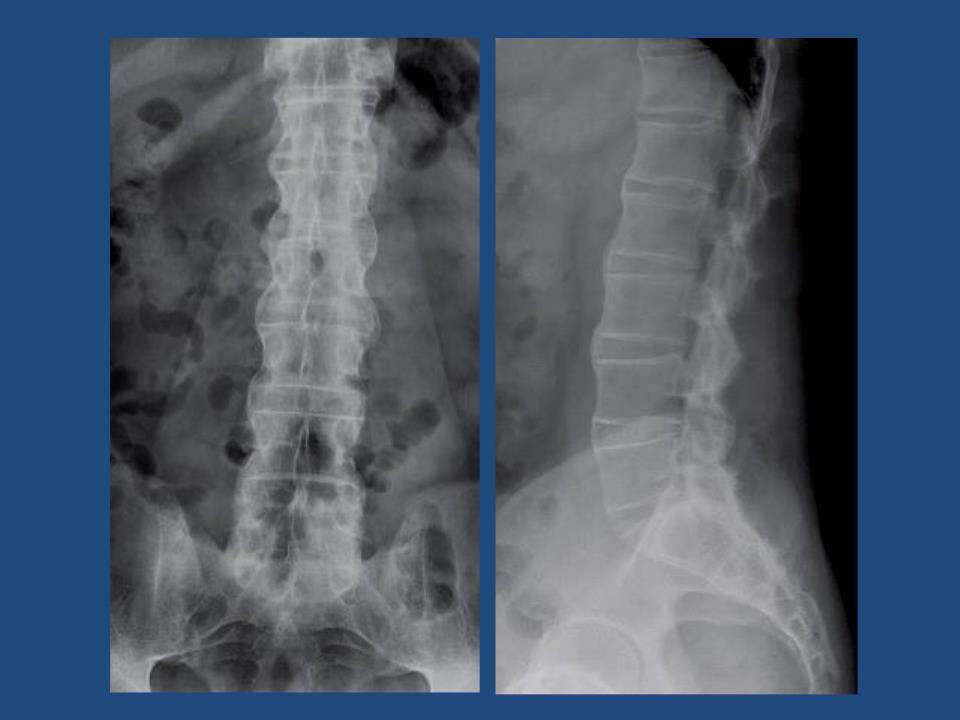

对于强直性脊柱炎的诊断方法,可以通过检查项目来进行诊断,较常见的检查项目包括ct扫描或者是x光线检查,这两种检查方法可以很好的判断出强直性脊柱炎的,类型和严重性,一旦进行确认之后,对于它的治疗方法,首先可以使用手术。